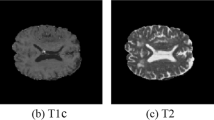

Predictive models in radiology can now be constructed with remarkable accuracy using an amalgamation of radiomics and artificial intelligence. To effectively prepare for surgical procedures and assess the progression of the tumor, accurate segmentation of gliomas is essential. The current study aims to address a segmentation of the whole tumor (WT), tumor core (TC), and enhancing tumor (ET), three partially overlap** regions of interest within the glioma with two variants, high-graded glioma (HGG) and low-graded glioma (LGG), made available through the BraTS 2019, 2020, and 2021 challenges. The traditional approach has been bypassed by focusing only on the network architecture, but rather the proposed research work is also concentrating on data pre-processing, augmentation, training, and testing strategies to improve the performance of the automatic brain tumor segmentation. UNet and its variants have recently been shown to be effective in automatically segmenting brain tumors from volumetric multi-modal magnetic resonance (MR) images. Motivated from the literature, an improved UNet + + framework (ResUNet + +) is proposed to segment multi-modal volumetric MR images of brain tumor. The ResUNet + + is a 3D (three-dimensional) encoder-decoder model where the encoder path is replaced with the pre-trained backbone of the ResNet50 model. Moreover, the standard convolutional blocks of the traditional UNet architecture are substituted with the 3D dense convolutional blocks, and in the decoder phase, convolutional layers are replaced by the convolutional transpose layers (ConvTranspose), outperforming the existing models in terms of segmenting the WT, TC, and ET in both HGG and LGG. The performance of the ResUNet + + framework is evaluated using five different performance parameters, and when compared with the state-of-the-art models, the results demonstrate the effectiveness of the framework.